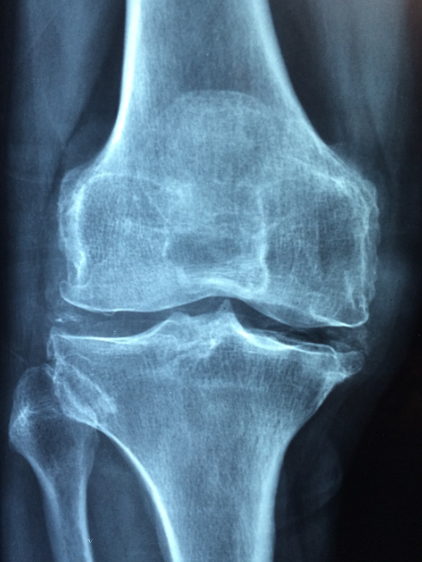

3. 골다공증 진단 방법

골다공증을 진단하려면 병원에서 전문적인 검사와 진단을 받아야 합니다. 주요 진단 방법은 다음과 같습니다.

- 골밀도 검사: 골밀도 검사는 뼈의 밀도를 측정하여 골다공증의 유무를 확인하는 방법입니다. 일반적으로 DXA(이중에너지 X선 흡수법) 검사를 사용합니다.

- CT 스캔: 정밀한 검사 방법으로, 뼈의 상태를 3D 이미지로 확인할 수 있습니다.